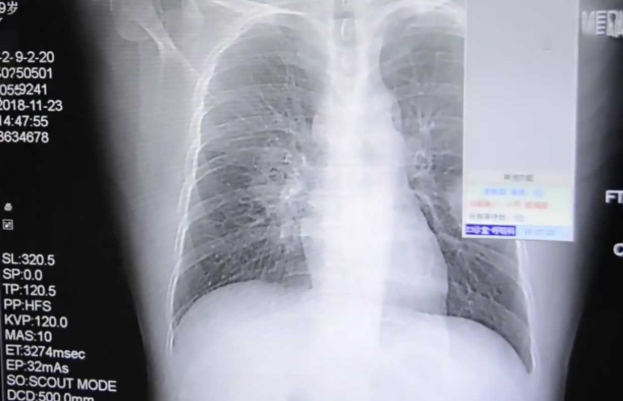

Η ακτινογραφία που υποβλήθηκε απέδειξε πως πάσχει από σοβαρή πνευμονική λοίμωξη και το νοσοκομείο επιβεβαίωσε πως ο λόγος ήταν η συνήθειά του.